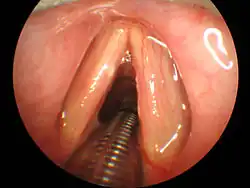

Classically, tracheal intubation has been performed utilizing direct laryngoscopy to obtain direct visualization of the vocal cords. There are multiple different laryngoscope blade styles, shapes, and lengths from which to choose based on patient anatomy and clinician preference.[9] In North America, the Macintosh blade is the most commonly used curved blade while the Miller blade is the most common straight blade.[9] Many modern laryngoscopes are equipped with a fiberoptic light source to aid in visualization. Regardless of blade shape, direct laryngoscopy technique involves passage of the laryngoscope through the mouth and into the back of the throat. Manipulation of the neck and lifting of the tongue allows for direct visualization of the larynx and vocal cords by the operator. Following visualization, the endotracheal tube can be passed along the blade, through the vocal cords, and into the trachea.[10]

Video Laryngoscopy

Multiple intubation tools are now available with built-in video technology, also known as video laryngoscopy.[9] The GlideScope model utilizes a curved laryngoscopic blade with an integrated camera connected to a large external monitor. The McGrath model has a compact design with a small display directly attached to the laryngoscopic blade. The operator introduces the video laryngoscope through the mouth with a technique similar to direct laryngoscopy. The larynx and vocal cords are visualized via the camera and the operator is able to pass the endotracheal tube through the vocal cords and into the trachea under direct visualization on the video monitor.[9] Studies have shown that when compared to direct laryngoscopy, video laryngoscopy resulted in fewer failed intubation attempts, especially in patients with known difficult airways.[11] Limitations of video laryngoscopy exist and prevent the exclusive use of this method over direct laryngoscopy. Excessive blood and saliva in the airway can cover the camera lens on the video laryngoscope and obscure effective visualization of the anatomy, preventing effective intubation attempts. This is of importance in patients with trauma to their airway, increasing the amount of blood present, and patients taking sialogogues, or drugs that increase the flow of saliva.[12]

Fiberoptic Intubation

In patients with known difficult airways, fiberoptic intubation can be considered. This technique involves the use of a flexible fiberoptic bronchoscope for visualization of the vocal cords. The bronchoscope can be passed directly into the trachea and the endotracheal tube can be threaded over the bronchoscope into position. This technique has various advantages over direct laryngoscopy and video laryngoscopy techniques. The fiberoptic scope is flexible and can be directed by the operator, allowing it to traverse the upper airway with minimal manipulation of the patient's neck. The operator can manipulate the device around obstructions in the upper airway, making the technique advantageous for patients with cancer or swelling in the upper airway. The device is relatively small compared to a laryngoscope and can therefore be implemented in patients with small mouth openings. Additionally, the fiberoptic scope can be passed through the nostril to provide visualization for a nasotracheal intubation. Lastly, fiberoptic intubation can be conducted in an awake patient with sufficient use of local anesthetics, which can prove useful in patients who would otherwise be unable to be anesthetized without having a secure airway in place beforehand. [9]